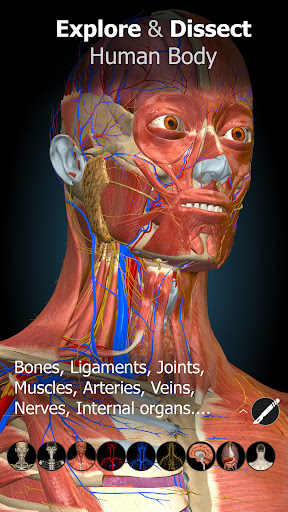

A true and totally 3D app for studying human anatomy, built on an advanced interactive 3D touch interface.

Features:

★ You can rotate models to any angles and zoom in and out

★ Remove structures to reveal the anatomical structures below them.

★ Switch on/off different anatomy systems

★ Bones

★ Ligaments

★ Joints

★ Muscles

★ Circulation (arteries, vein and heart)

★ Central nervous system

★ Peripheral nervous system

★ Sense organs

★ Respiratory

★ Digestive

★ Urinary

★ Reproductive ( both male and female)